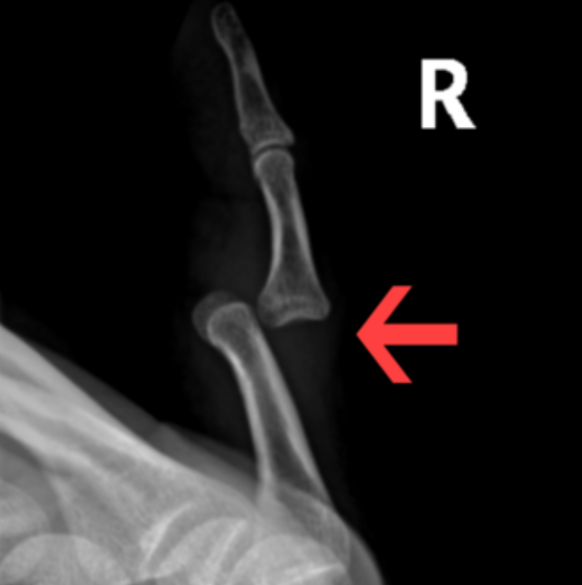

What Is a Joint Dislocation?

A joint dislocation occurs when the bones that form a joint are forced out of their normal position. This can damage surrounding muscles, ligaments, tendons, nerves, and blood vessels.

Signs You May Have a Dislocated Joint After a Car Accident

Some joint dislocations are obvious, while others may be partial or subtle. Common signs include:

- Visible deformity or abnormal positioning

According to crash injury data, shoulder dislocations are the most common joint dislocation in car accidents, but other frequently affected areas include:

- Fingers

Any joint dislocation can lead to long-term complications if not properly treated.